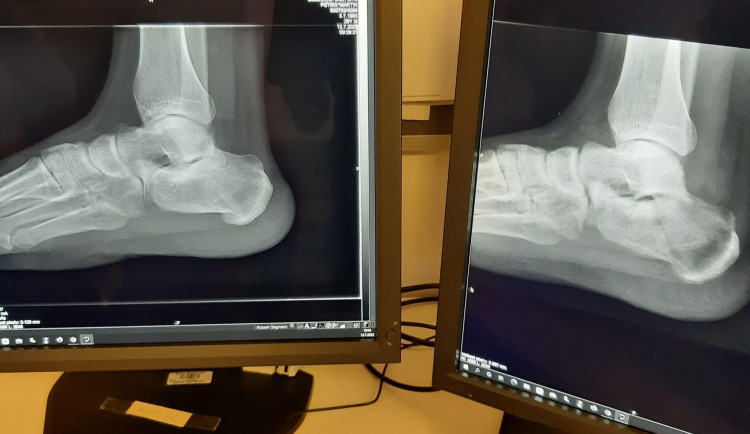

Šetrnější přístroje, které vytvářejí kvalitní rentgenové snímky, mají v brněnské nemocnici Milosrdných bratří. Nové digitální rentgeny znamenají pro pacienty až o polovinu nižší radiační zátěž než obvykle. Zařízení vyšla na dvanáct milionů korun.

Zatímco před desítkami let museli zaměstnanci radiologických oddělení vyvolávat rentgenové snímky v temné komoře prostřednictvím zdlouhavého procesu, dnes trvá pořízení fotografií jednu vteřinu. Ještě lepší pohled na snímky se nyní naskytne lékařům nemocnice v brněnské Polní ulici. Pracovat se učí s moderními digitálními rentgenovými přístroji. Ty používají k detekci záření japonské receptory Canon, kterými se “prosvěcují” vyšetřované orgány.

Právě firma Canon, jež je známá především mezi fotografy, se čím dál více prosazuje v medicíně. „Nové rentgenové zařízení má až o polovinu nižší radiační zátěž pro pacienta a dvakrát vyšší rozlišení snímků než původní zařízení,“ informovala zastupující primářka radiodiagnostického oddělení nemocnice Milosrdných bratří Zdena Kadlecová.